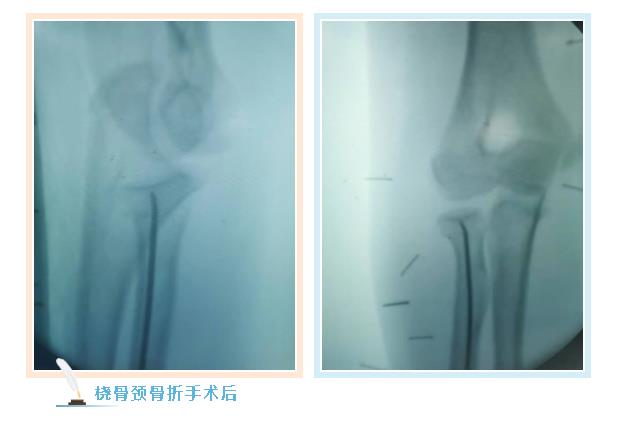

887700线路检测网骨伤二科副主任张永青仔细查看孩子患处,安排其进行放射拍片检查,结果为左侧桡骨颈骨折,根据孩子的骨折状况,张主任认为保守治疗很难做到理想复位,且复位后较难维持良好位置,可能会影响将来前臂的旋转功能,建议孩子尽快接受手术治疗,孩子的家长担心传统手术切口大,孩子所受痛苦多,犹豫不决,张主任与家长沟通,孩子要接受的不是传统的开放手术,而是“骨折闭合复位弹性髓内钉内固定”微创手术,手术只需要一个0.5-1厘米左右的切口就可以达到满意的效果,家长立即同意接受手术治疗。手术非常成功,术后第三天,周周出院。

张永青介绍,“弹性髓内钉技术”是儿童骨科界的一次革命,被誉为上帝赐予长骨骨折儿童的礼物,该项技术可在保护骺板不受损伤的前提下,利用多点固定的原理,微创、有效地治疗4-12岁的四肢骨折患儿,该技术利用钛合金或不锈钢良好的弹性、恢复力将作用于长骨的3个接触点转换成推力和压力,从而使骨折复位,有足够的力量抵抗骨折端移位作用,该方法不需要剥离骨膜和切开骨折端,不干扰骨骺生长,也不破坏骨折端血运,弹性固定、局部微动、创伤小、骨折愈合快,术后3周即可进行功能锻炼,术后1个月功能恢复正常。